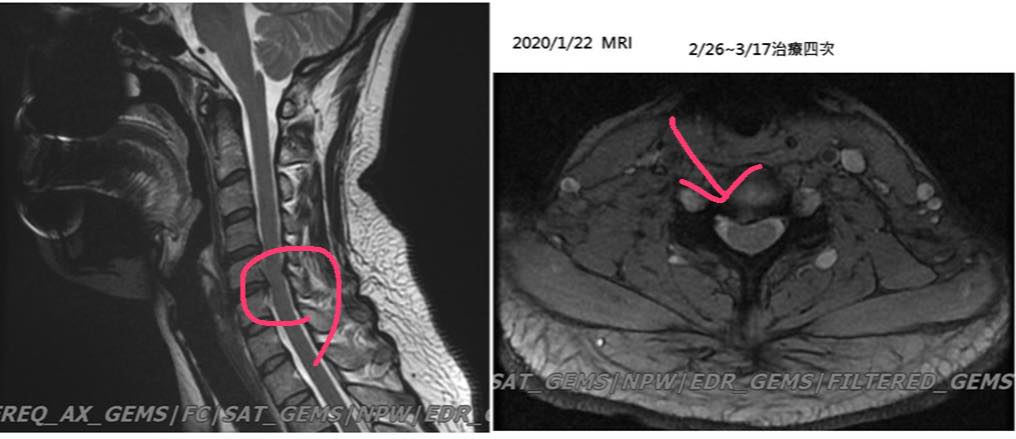

Cervical Spine Treatment Cases 頸椎治療案例 感謝新竹市羅小姐熱情見證 頸椎整合中醫微創療法逆轉勝 2020.03.18 感謝台北市👮♀️陳大哥熱情見證 困擾三年頸椎疼痛逆轉勝 騎機車手麻到無法煞車劇痛不... 2020.03.13 感謝台中市許大姐熱情見證 頸椎壓迫導致右臂酸麻痛五個月 脊椎整合中醫微創逆轉勝 2020.03.12 史上第一次碰到全聾啞人士聘用手語翻譯人員來診所接受脊椎整合中醫維創! 2020.02.22 #嚴重的頸椎反弓醫案 #疼痛超過半年左側肩膀麻痛連手臂 #感謝葉先生熱情見證 2020.02.22 #頸椎痛到無法睡覺怎麼回事 #神經根型頸椎病醫案 #感謝台北吳小姐熱情見證 #脊椎整合... 2020.02.13 #頸椎間盤突出痛到右手完全沒力 #神經根型頸椎病合併輕微脊髓壓迫 #原本考慮裝設人工... 2020.02.07 #脊髓型嚴重壓迫患者 #可能非針刀類型患者 2020.01.23 #頸椎壓迫醫案見證 #脊椎整合中醫微創療法原理說明 #感謝新竹余先生熱情見證 #什麼症... 2020.01.22 #頸椎壓迫神經根醫案 #疼痛超過三年以上 #來診前幾個月大痛到無法睡覺 #感謝新莊陳大... 2020.01.10 #感謝台大學長熱情見證頸椎針刀療法 #脊椎整合中醫微創療法 2019.12.17 #感謝宜蘭李大哥熱情見證 #神經根型頸椎病痛到上臂肩膀麻痛 #原本想說熱愛的衝浪可能... 2019.12.08 😂原本都準備要去開刀了! 😢醫學中心報價兩節椎間盤報價52萬 😄感謝苗栗患者熱情見證... 2019.11.22 ❇️頸椎間盤突出痛到完全無法洗頭 #核磁共振證實C4C5突出壓迫 #上樓梯頭往後面抬就誘發... 2019.11.13 #頸椎痛到無法睡覺怎麼回事 #原本認真考慮開刀治療 #感謝雲林患者熱情北上見證 #脊椎... 2019.10.21 ← 上一頁 6 7 8 9 10 下一頁 →